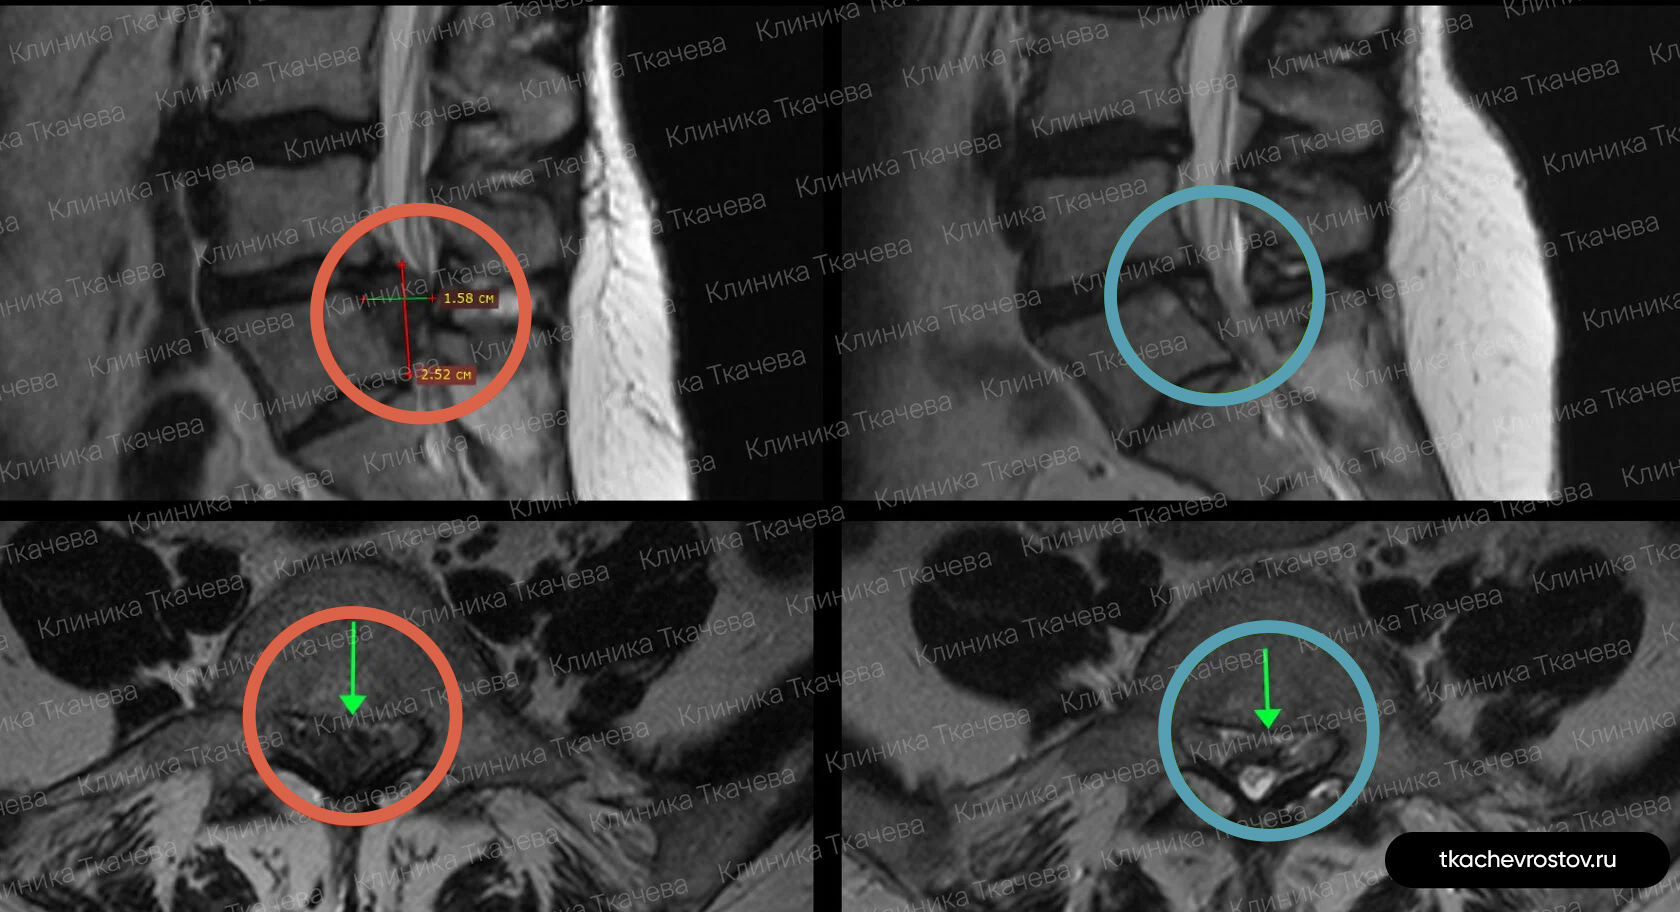

Грыжа в поясничном отделе L4-L5

Мужчина. Межпозвонковая грыжа в сегменте L4-L5 1.5 х 1.7 см с абсолютным стенозом позвоночного канала. Никакое лечение не помогло, отправили вначале к психиатру, а потом к нейрохирургу.

ДО:

- Интенсивная боль в пояснице, с эпизодическими прострелами

- Ограничение движений в пояснице

- Нарушения сна

- Снижение бытовой и социальной активности

ПОСЛЕ 1 курса:

✓ Наступила частичная резорбция грыжи

✓ Наступило улучшения общего состояния.

ПОСЛЕ 2 курса:

✓ Наступила полная резорбция грыжи

✓ Небольшое восстановление высоты межпозвонкового диска (регенерация пульпозного ядра)

Лечение грыжи заняло 8 месяцев. Было проведено 2 курса лечения по 12 дней.